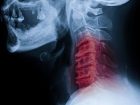

「首ポキ」は今すぐ止めるべき!? 関節を鳴らした瞬間に脳卒中や植物状態に…死亡例...

指や手足、腰など体の関節を”ポキッ”と鳴らすのが、い...